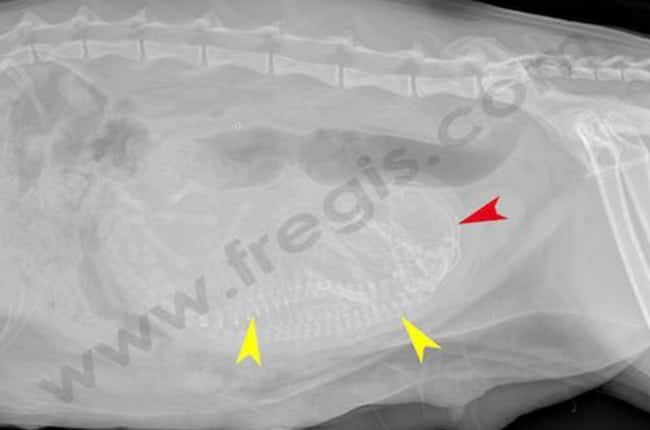

A partir de 38 à 40 jours, la minéralisation des squelettes fœtaux se développe. Dès 50 jours, un diagnostic radiographique de certitude et un comptage beaucoup plus fiable du nombre de fœtus est possible.